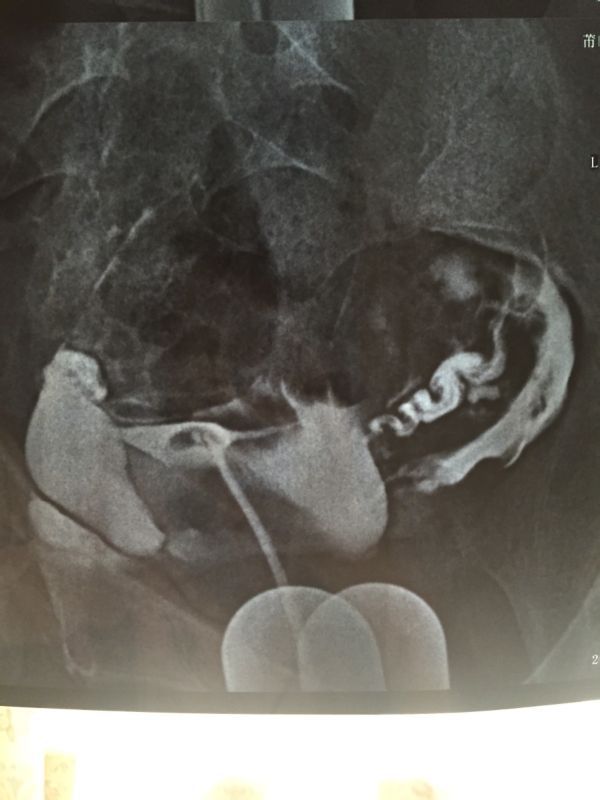

原发性不孕,碘海醇造影,双侧输卵管显示迂曲,伞端见造影剂聚积,造影剂通过双侧输卵管进入盆腔弥散,部 分呈团状显示,考虑:双侧输卵管伞端粘连,不全阻塞,请问要做手术吗?手术成功率高吗?怀孕几率高吗?急盼答复 点击展开 匿名用户 2015-03-29 18:16 为您推荐: 其他回答 你好,如果双侧输卵管不是完全堵塞的话,做手术后怀孕的几率非常大。建议你选择手术治疗,如果害怕手术失败可以选择做试管婴儿。 天使7737 2015-03-29 22:28 相关问题 右侧输卵管部分峡部显影 左侧输卵管走行迂曲,造影剂流速正常,数秒钟后可见中量造影剂弥散入盆腔,涂布 右侧输卵管部分峡部显影 左侧输卵管走行迂曲,造影剂流速正常,数秒钟后可见中量造影剂弥散入盆腔,涂布 右侧输卵管部分峡部显影 左侧输卵管走行迂曲,造影剂流速正常,数秒后可见中量造影剂弥散入盆腔,涂布欠